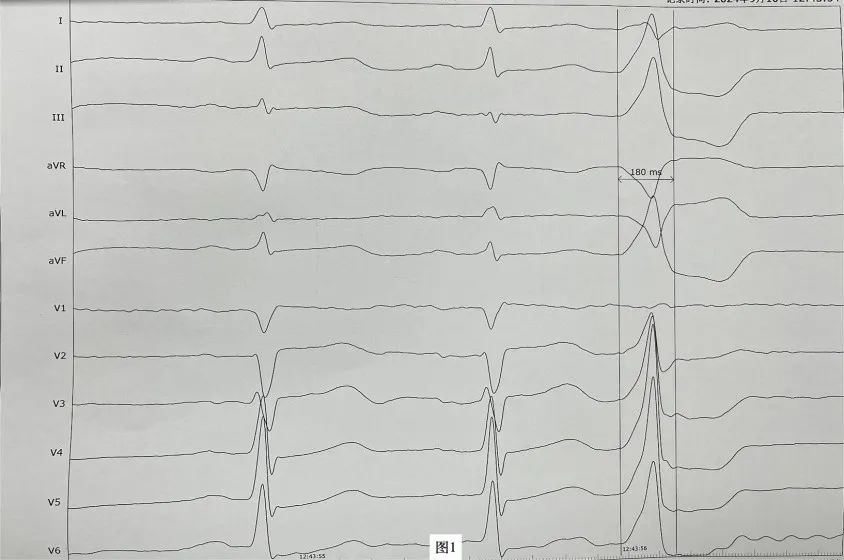

李先生(化名),近年来一直受病痛折磨,反复心悸、胸闷发作,夜间难以入睡,多次在外院就医治疗效果均不理想。近日,李先生再次因心悸症状明显慕名来到财神捕鱼 心血管内科二病区周明礼门诊就诊。患者心电图检查提示有室性早搏,24小时动态心电图提示室早超过40000次,占总心跳40%左右。经诊断,患者有频发室性早搏,心悸症状因室早所致。周明礼认真分析病情后,告诉患者这个病不用开刀,在清醒状态下,从腿部穿刺血管将消融导管送入心脏进行心脏射频消融治疗就可以得到根治,并且术后第二天就可以下床走路。但因该患者早搏起源左室summit区域(图1),位置刁钻,难度较大,能够成功手术的财神捕鱼 屈指可数。财神捕鱼 心血管内科二病区开展射频消融手术多年,该区域室性早搏消融成功率较高,受疾病困扰多年的患者听到这个消息很高兴,并表示辗转就医多年终于看到了希望,决定在财神捕鱼 进行手术治疗。

病历显示,该患者左室summit区(LVS)包括心外膜部和心内膜部(图2):心外膜部为左冠状动脉回旋支(LCx)、前降支(LAD)和心大静脉(GCV)形成的心外膜三角形区域,因心大静脉和前室间静脉(AIV)都位于此处,又可称为GCV/AIV区。GCV将心外膜LVS分为上部和下部,上部邻近冠状动脉且覆盖心外膜脂肪组织,故也称为消融不可到达区域,而下部则为心外膜导管消融可能到达区域。该区域位于左室出口部外侧,距冠状动脉较近,且部分位置表面覆盖厚脂肪层,此处室早的消融不仅风险大而且消融导管难以到达,故一直被电生理界认为是室早消融的难点。起源于该区域的室早一直是心律失常最具挑战性的起源部位之一,消融成功率低,治疗难度大。然而,干性心包穿刺外膜消融技术的出现,为解决这一难题提供了新的希望。